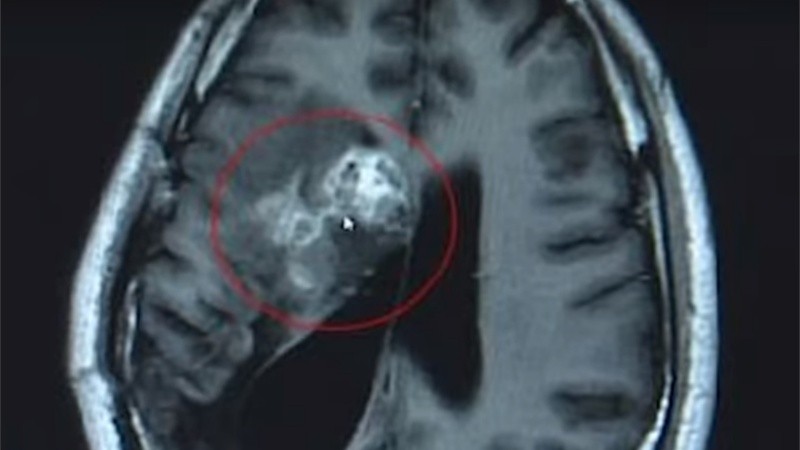

Un chino fue operado a finales del pasado mes en un centro médico de la provincia de Guangdong, donde le extirparon de su cerebro un parásito vivo de doce centímetros de largo. El gusano se alimentó de sus tejidos durante quince años. Aparentemente, todo se inició por comer caracoles que no estaban bien cocidos.

Según publicó Russia Today, el neurocirujano Gu Youming, quien dirigió la operación que duró más de dos horas, explicó que si no extraían el parásito, la tenia habría seguido comiendo la masa cerebral del hombre, lo que podría haber producido parálisis o la muerte.